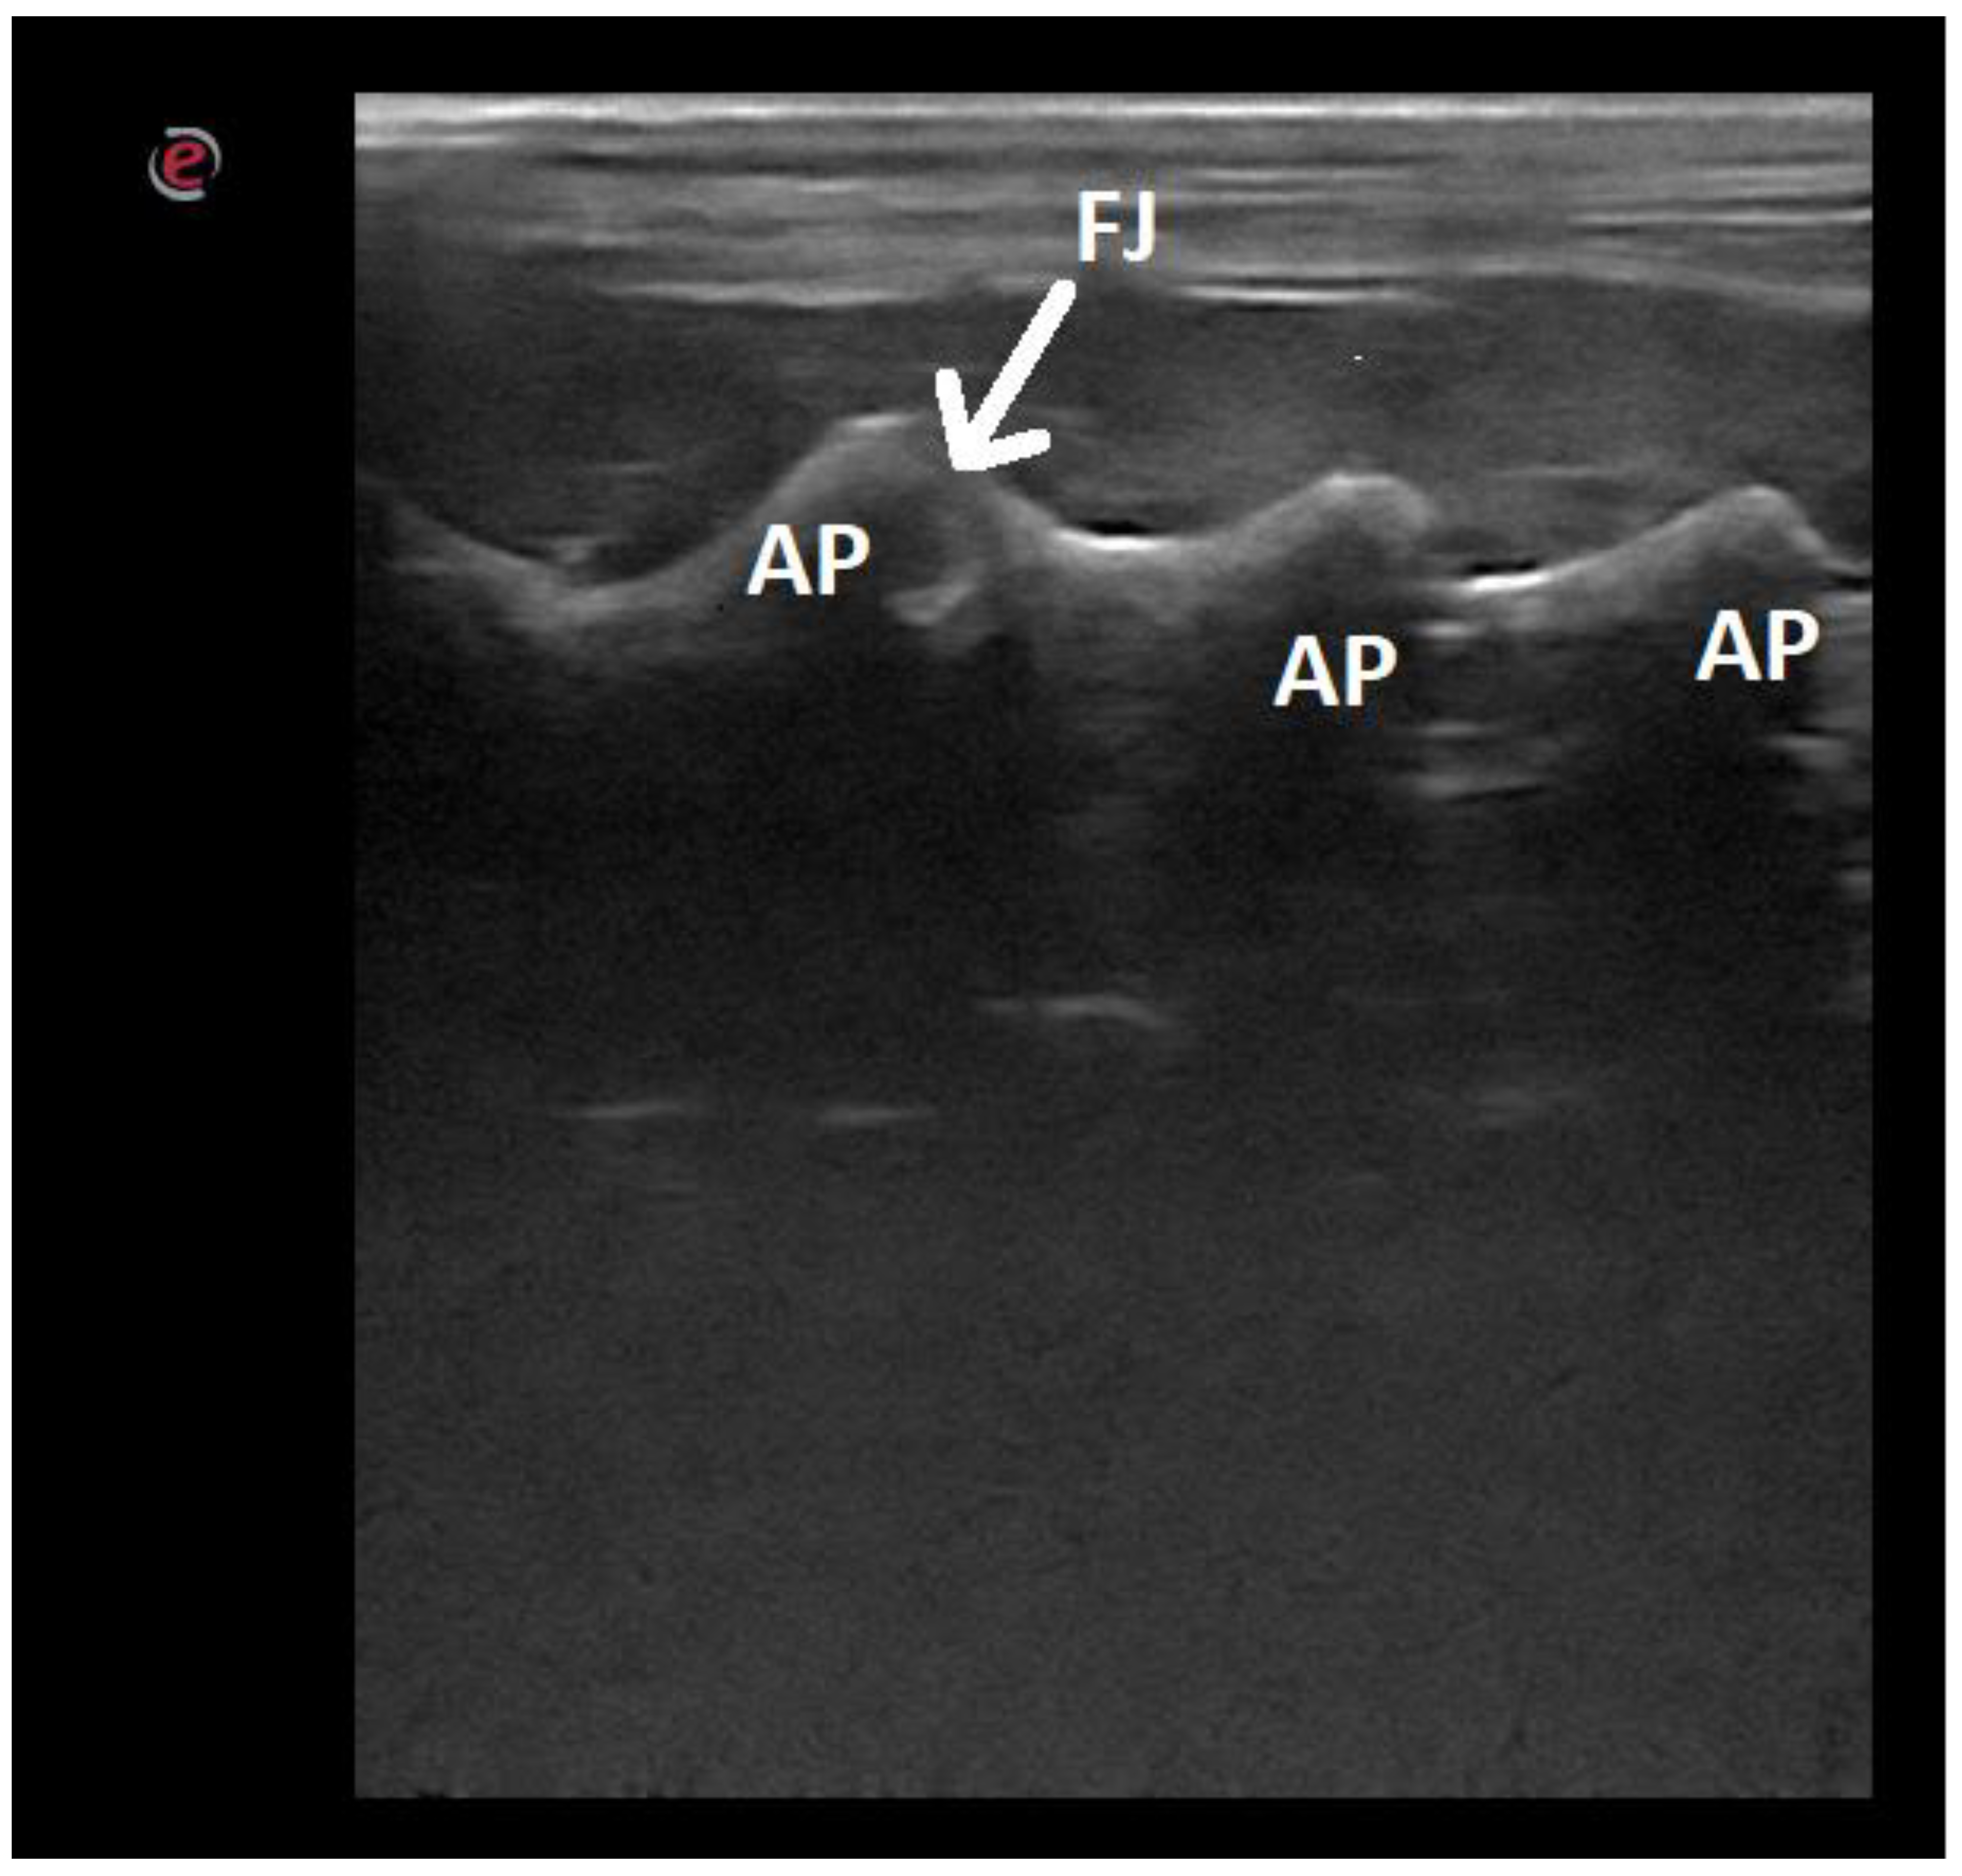

| Articular processes | 12/52.17 |

| Articular processes | 7/30.43 |